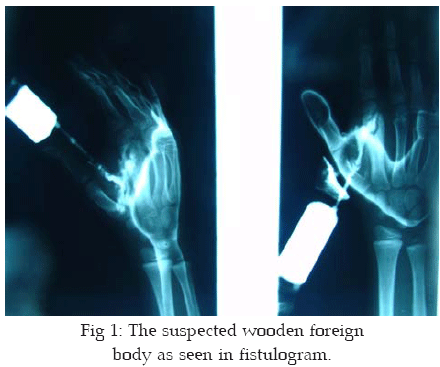

Physical examination showed multiple dirty yellow exerting wounds, with reduction in the range of movement at the second metacarpal phalangeal joint. Laboratory examinations showed normal CBC and ESR. His previous X-ray showed lytic lesions with destructive changes in the cortex on the radial side. Another X-ray was taken which showed spindle lytic lesion with sclerotic wall without growth plate involvement in the metaphyseal area. Fistulogram examination using radio-opaque agents revealed a 10 x 5 mm foreign body in the second metacarpal bone (Fig-1). Surgical incision showed a swollen wooden foreign body in his 2

nd metacarpal bone. Surgical removal and debridement of the granulation tissue surrounding it were performed using dorso radial incision at the second metacarpal bone. A window in the bone was left open together with loose suturing was made to aid easy drainage of any excretions of the wound. Pathological report on the specimens examined showed an inflammatory lesion with many giant cells. Culture results showed negative for any infection. The wound healed normally and the patient was discharged seven days later. Sinus secretions disappeared three weeks after his operation and the range of movements became normal.